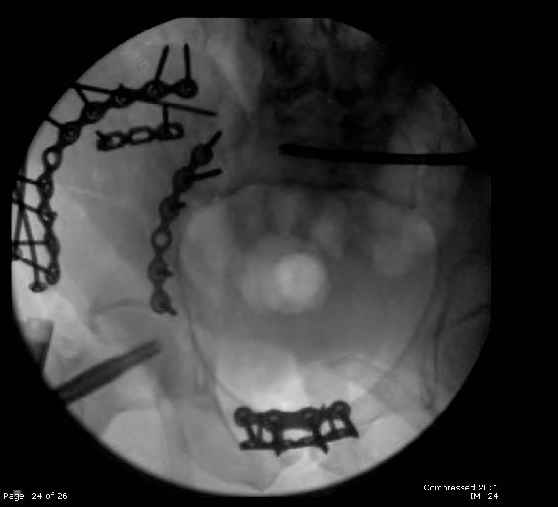

Here are the postop fluoros.

First exposed symphysis & clamped w/Faraboeuf as close to anatomic as possible.

Then extended to R ilioinguinal,really just the lateral window.

Reduced the triangular wedge piece of iliac wing to posterior intact ilium (crescent), held w/k-wire, then used 3-hole push plate to keep from moving, lagged from lat-med w 3.5 screw.

Then 6-hole plate along brim with 1 screw in R sacral ala. Then lagged 2 screws along crest A --> P. finally 10-hole plate along inner aspect of crest. R posterior ilium still a bit stepped off.

Symphysis then 'fine-tuned' & reduced as close as possible to anatomic (but, still with forward rotation of R hemipelvis - or, is it extension?) Accepted that amount of deformity and plated symph

with 4-hole symphyseal plate.

Fluoroed L SI joint and it seemed stable, but wide. So, applied c-clamp to try to squeeze down L SI joint (and note, on the last slide attached, that it's still wide), and got it closer. Single perc Iliosacral screw 40mm thread.

Applied second plate anteriorly on symphysis as I wasn't confident L SI was as stable as it could be and wanted to protect it better.